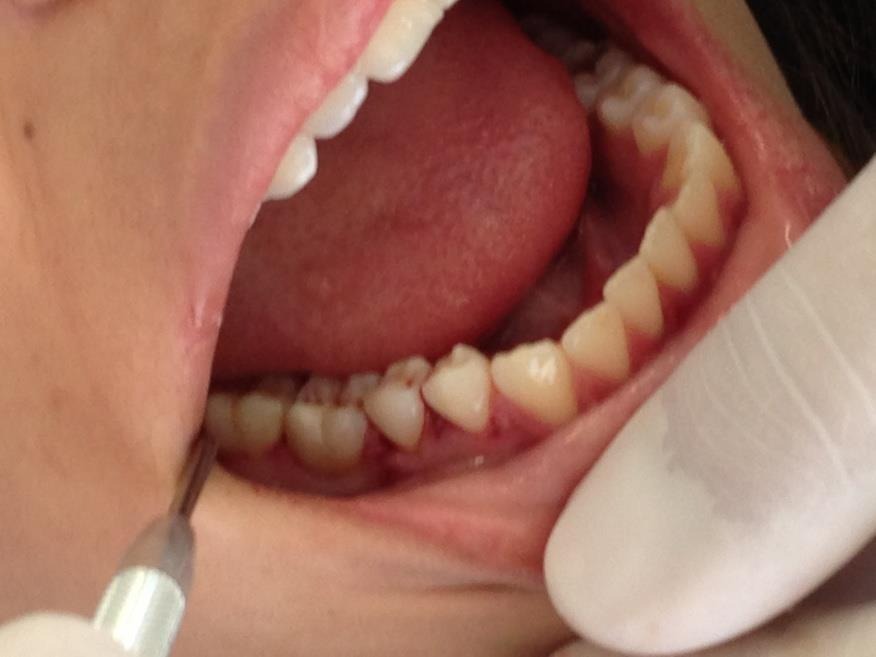

Longo prazo de proservação avaliando imagens radiográficas bem como exames clínicos, retirada da contenção após 60 dias, só então afirmar sucesso no procedimento cirúrgico realizado. (figura 10 e 11).

Figura 11 – após remoção da contenção.